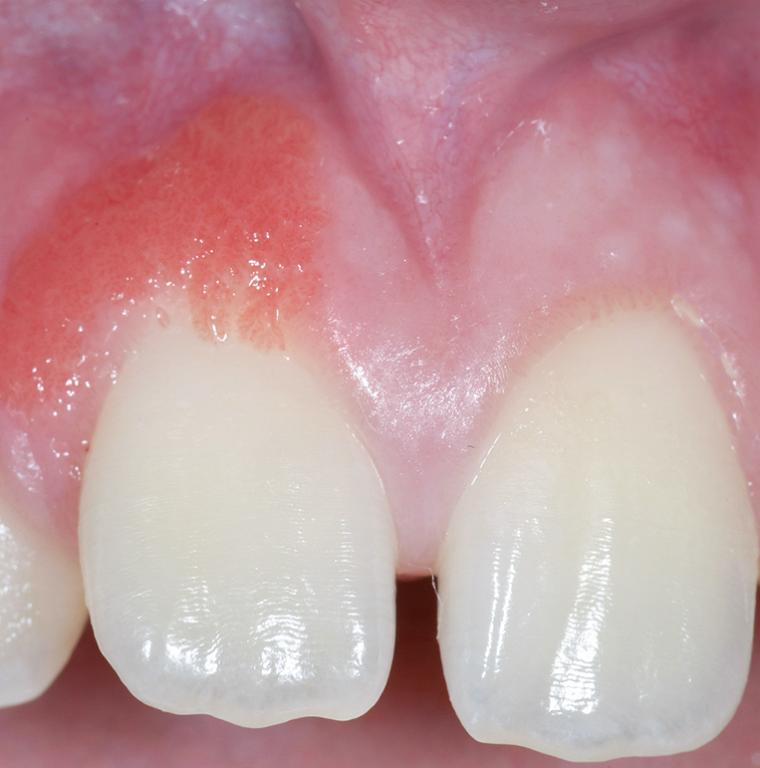

Deze nascholing is bedoeld om preventieassistenten te ondersteunen bij het herkennen van veelvoorkomende afwijkingen van het mondslijmvlies en tandvlees. In de praktijk is het niet haalbaar om álle mogelijke mondafwijkingen paraat te hebben; daarvoor zijn atlassen en leerboeken beschikbaar. Wel is het belangrijk om afwijkingen tijdig te signaleren. De opbouw van deze e-learning sluit aan bij de dagelijkse praktijk. Er wordt aandacht besteed aan ulceraties, gepigmenteerde afwijkingen, witte, wit-rode en rode laesies, en zwellingen. Daarnaast komt een apart onderdeel aan bod over tandvleesafwijkingen die niet plaque-gerelateerd zijn. Tot slot wordt ingegaan op de klacht van tong- en mondbranden. Een goed uitgevoerd mondonderzoek – inclusief inspectie van tong en mondbodem – wordt als bekend verondersteld. Deze nascholing helpt je jouw observatievermogen te versterken en je rol in vroegsignalering te verdiepen.